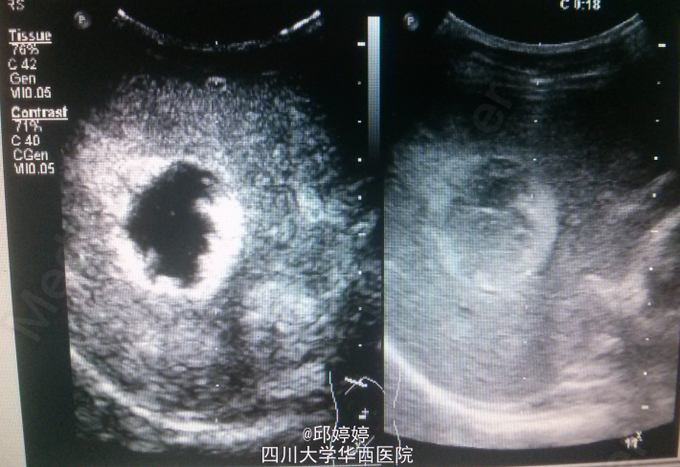

患者,男,36岁,体检超声发现肝内数个稍强回声团,较大位于右后叶,大小约5.0x3.7cm,上述团块边界清楚,形态较规则,较大者推挤右肝静脉,部分内部回声呈网格状;超声造影:团块动脉期呈环状结节样高增强(图1),门脉期持续向内充填(图2),实质期呈等增强(图3)。 讨论:血管瘤典型的超声造影表现特点明显,易于与其他良性或恶性病变相区分。